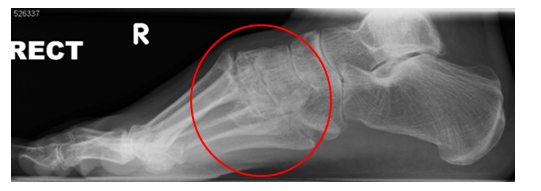

Lisfranc injury with the tearing of ligaments, fracturing of the metatarsal bases and loss of alignment.

The X-ray above shows loss of alignment across the midfoot joints, irregular joint surfaces as a result of multiple fractures.